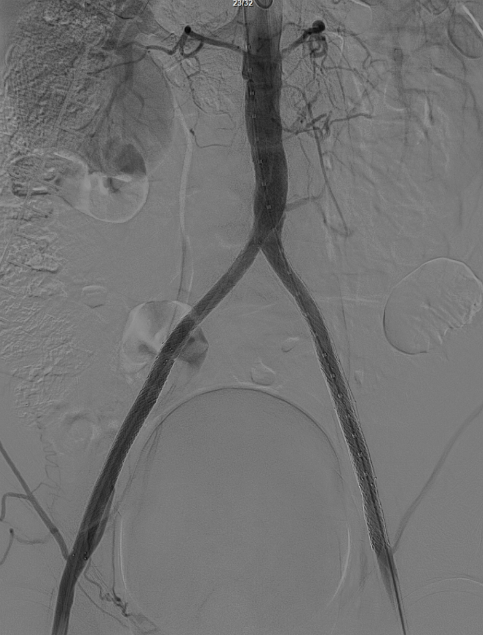

右侧髂外动脉存在残存狭窄,因该部位无原有裸支架覆盖,为节省治疗费用,选择植入1枚直径8mm的裸支架,并采用8mm球囊进行后扩张。

即时效果:造影显示腹主动脉、双侧髂总/髂外动脉及股动脉通畅。

3个月复查:右侧股动脉完全再通,无残存狭窄;CTA显示腹主动脉、双侧髂动脉及远端股动脉通畅,双侧ABI>1.0;左侧髂动脉开口打开不全(推测与对吻球囊直径选择有关,原用8mm,若选10mm可能避免),因患者无症状,暂密切随访,远期若再狭窄可采用10mm球囊扩张。